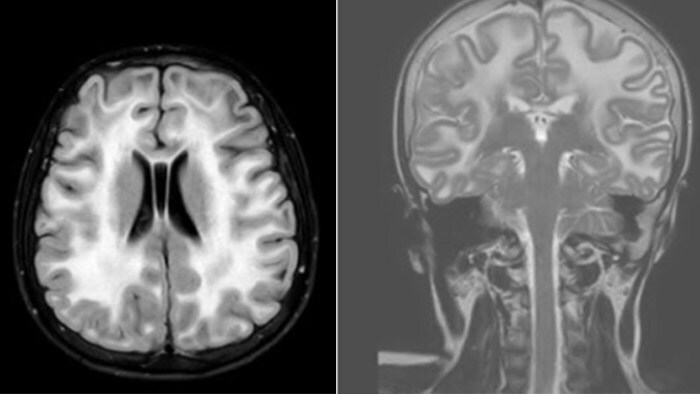

Hydrocephalus post hemorrhagic Both pictures show a ventriculoperitoneal shunt. With our previous scanner our hydrocephalus protocol needed about 25 min. With Ambition the examination time is about 14 min. including a CSF PCA sequence to show flow in the aqueduct.

Leukodystrophy in a teenager

Rostral meningitis and arachnoiditis Both images are from the same 3D T1-weighted post contrast sequence in a newborn, under treatment.